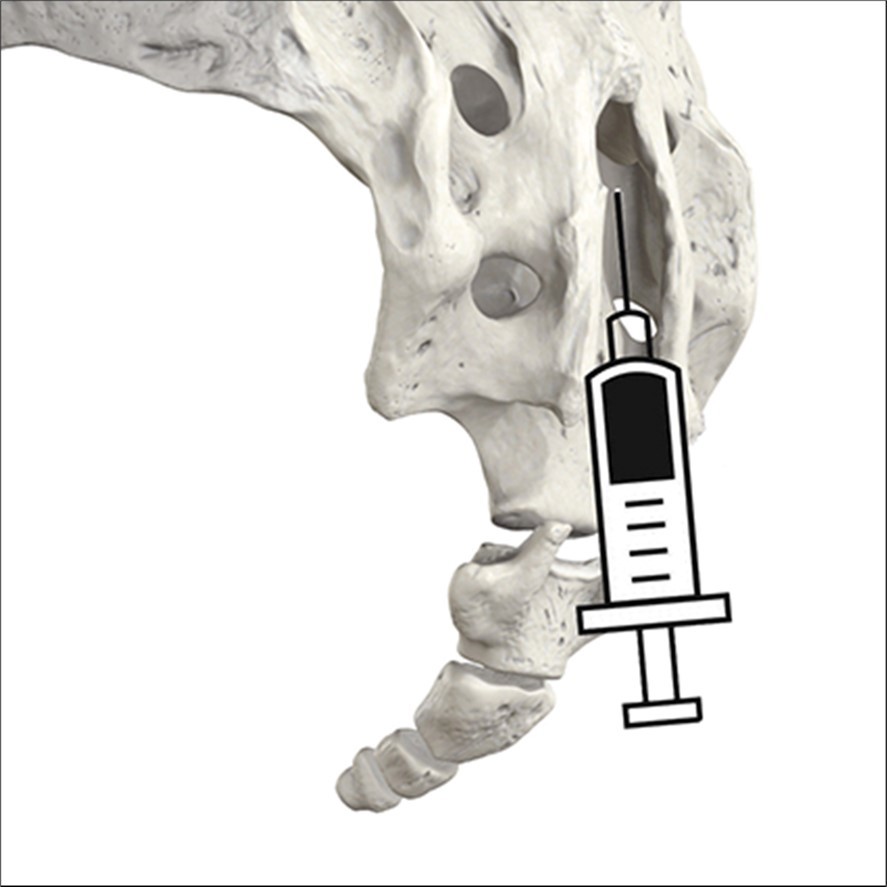

sacral injection involves injecting a steroid medication into the epidural space (Figure 1), which is the area around the spinal nerves. A caudal injection can help treat various conditions that cause nerve pain, such as herniated discs, spinal stenosis, sciatica, and post-surgery syndrome.

Figure 1.posterior view of the injection in the hiatus.